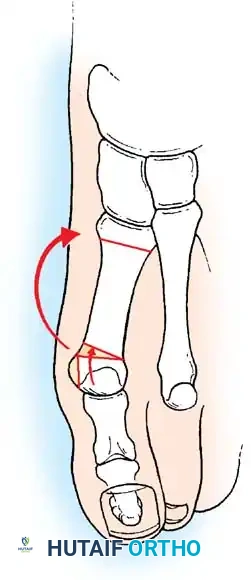

Hallux valgus (lateral deviation of the great toe) is not a single disorder, as the name implies, but a complex deformity of the fi rst ray that frequently is accompanied by deformity and symptoms in the lesser toes (Fig. 78-1). Often the angle between the fi rst and second metatarsals is more than the 8 to 9 degrees usually considered to be the upper limits of normal. The valgus angle of the fi rst metatarsophalangeal joint also is more than the 15 to 20 degrees considered to be the upper limits of normal (Fig. 78-2). If the valgus angle of the fi rst metatarsophalangeal joint exceeds 30 to 35 degrees, pronation of the great toe usually results. With this abnormal rotation, the abductor hallucis, which is normally plantar to the fl exion-extension axis of the fi rst metatarsophalangeal joint, moves further plantarward (Fig. 78-3). In this case, the only restraining medial structure is the medial capsular ligament with its capsulosesamoid portion (inserting into the base of the proximal phalanx) (Fig. 78-4) and capsulophalangeal portion (inserting into the plantar plate). The adductor hallucis, which is unopposed by the abductor hallucis, pulls the great toe further into valgus, stretching the medial capsular ligament (particularly the capsulosesamoid), attenuating this structure, and allowing the metatarsal head to drift medially from the sesamoids. In addition, the fl exor hallucis brevis, fl exor hallucis longus, adductor hallucis, and extensor hallucis longus increase the valgus moment at the metatarsophalangeal joint, further deforming the fi rst ray. The deep transverse intermetatarsal ligament runs between the plantar plates at the metatarsophalangeal joints and does not insert into bone on the adjacent sides of the metatarsal heads. Finally, the sesamoid ridge on the plantar surface of the fi rst metatarsal head (the crista) fl attens because of pressure (abutment) from the tibial sesamoid (Fig. 78-5). With this restraint lost, the fi bular sesamoid displaces partially or completely into the fi rst intermetatarsal space (see Fig. 78-2). In this situation, the patient is bearing less weight on the fi rst ray and more on the lesser metatarsal heads, increasing the likelihood of transfer metatarsalgia, callosities, and stress fracture of a lesser metatarsal.

Two other anatomical variants involving the articular surface of the fi rst metatarsophalangeal joint can lead to hallux valgus. In the fi rst variant, the articular surface of the metatarsal head is offset, resembling a scoop of ice cream sitting at an angle on a cone (Fig. 78-6). This has been described as the distal metatarsal articular angle (see Fig. 78-8). In the second, the articular angle of the base of the proximal phalanx in relation to its longitudinal axis is offset. This has been described as the phalangeal articular angle. Although the normal range of these angles is generally considered to be 7 to 10 degrees for the phalangeal articular angle and 10 to 15 degrees for the distal metatarsal articular angle, exact measurements are diffi cult to reproduce because of the variability of radiographic and measurement techniques. Increasing evidence indicates, however, that the failure to correct these two deformities, especially the distal metatarsal articular angle, can cause unsatisfactory results after surgery in some patients. Forceful straightening of the hallux should be avoided if it sacrifi ces tarsalgia. The entire forefoot must be evaluated for these multiple components of hallux valgus before surgical planning is complete and recommendations can be made to the patient. The controversy continues over which deformity is the essential lesion in hallux valgus: metatarsus primus varus or lateral deviation of the great toe. Each is incriminated as the cause of the other. The strongest data probably support lateral deviation of the great toe as the primary deformity in most patients, followed by medial angulation of the fi rst metatarsal, but metatarsus primus varus may be the principal cause in adolescents. Further controversy surrounds the role of footwear as the prime offender in the development of hallux valgus. Most orthopaedic surgeons have seen unilateral hallux valgus when both feet are clinically and radiographically the same structurally except that one foot has a bunion deformity and the other foot is normal. Evidence supports that hallux valgus may be familial, especially when it occurs in adolescents. Although no study of shod and unshod societies has implicated inappropriate footwear as the sole cause of hallux valgus, after genetic factors, binding, unphysiologically designed footwear probably is the major cause in modern societies. Hypermobility of the fi rst ray also has been suggested as a causative factor in the development of hallux valgus and fi rst metatarsal varus, but this is controversial. Coughlin and Shurnas, Myerson and Badekas, King and Toolan, and Faber et al. offer excellent discussions of this problematic area. Finally, certain anatomical and structural abnormalities almost certainly play a causative role in hallux valgus. Pronated fl atfeet, abnormal insertion of the posterior tibial tendon, increased obliquity of the fi rst metatarsomedialcuneiform joint, an abnormally long fi rst ray, incongruous articular surfaces of the fi rst metatarsophalangeal joint, and excessive valgus tilt of the articular surface of the fi rst metatarsal head and proximal phalangeal articular surface may contribute singly or in combination to the deformity and infl uence the recommended treatment. Hypertrophy of the medial eminence has been described as a component of hallux valgus deformity since the earliest reports; however, more recent investigations, including those of Thordarson and Krewer, have found that bony proliferation is not a component of the pathoanatomy of hallux valgus and that the prominence of the medial eminence results from the combination of metatarsus primus varus and medial deviation that uncovers the articular surface. Thordarson and Krewer compared radiographs of 50 feet in patients who had surgery for hallux valgus deformity with radiographs of 50 feet from a control group without hallux valgus deformity and found little difference in the average width of the medial eminence (4.4 mm and 4.1 mm). With more than 130 operations recommended for the treatment of hallux valgus, it is practical to describe only

a congruent metatarsophalangeal articulation; phalangeal osteotomy or distal metatarsal osteotomy, rather than tightening of the medial capsular repair, should be used for further correction. The valgus posture of the great toe frequently causes a hammer toe–like deformity of the second toe (Fig. 78-7). In addition, the splaying of the forefoot makes the wearing of shoes more diffi cult; with shoes that have a narrow toe box, corns often develop, as does bursal hypertrophy over the medial eminence of the fi rst metatarsal head (bunion). With valgus subluxation of the fi rst metatarsophalangeal joint, osteoarthritis frequently develops. In this case, the entire spectrum of hallux valgus is present: varus deformity of the fi rst metatarsal, valgus of the great toe, bunion formation, arthritis of the fi rst metatarsophalangeal joint, hammer toe of one or more toes, corns, calluses, and meta-